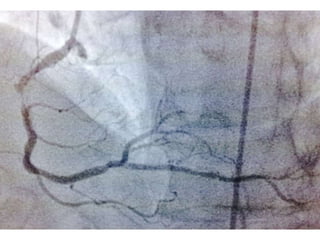

CUADRO CLINICO: INFARTO AGUDO DEL MIOCARDIO CON ELEVACION ST DE

LOCALIZACION ANTERIOR EXTENSO. REFERIDO DESDE JUIGALPA A LAS 8 HORAS

DESPUES DEL EVENTO

TA 110/ 50 mm Hg. FC 117/min Fr 19/ min

Glucosa 245 mg /dL. Colesterol total 277 mg/dL, LDL 170 mg d/L

Creatinina 1.6mg/dL. Marcadores cardiacos de daño miocárdico elevados

EXAMEN FISICO: Killlip KimbalI II.

CLINICAMENTE CON ANGOR E INESTABILIDAD HEMODINAMICA

CASO CLINICO #2 MASCULINO 70 AÑOS DE EDAD GANADERO, ACTIVO FISICAMENTE DIABETES TIPO 2 DESDE HACE 15 AÑOS. CONTROL METABOLICO POBRE HIPERTENSION ARTERIAL CONTROLADA CON ATENOLOL. CUADRO CLINICO: INFARTO AGUDO DEL MIOCARDIO CON ELEVACION ST DE LOCALIZACION ANTERIOR EXTENSO. REFERIDO DESDE JUIGALPA A LAS 8 HORAS DESPUES DEL EVENTO TA 110/ 50 mm Hg. FC 117/min Fr 19/ min Glucosa 245 mg /dL. Colesterol total 277 mg/dL, LDL 170 mg d/L Creatinina 1.6mg/dL. Marcadores cardiacos de daño miocárdico elevados EXAMEN FISICO: Killlip KimbalI II. CLINICAMENTE CON ANGOR E INESTABILIDAD HEMODINAMICA